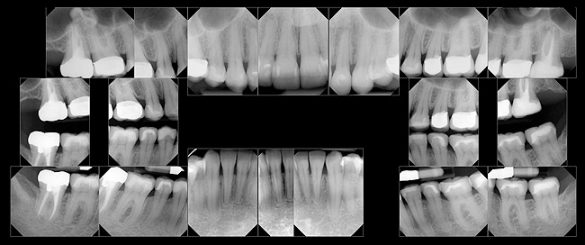

PARODONTAL: Evaluarea parodontală a evidenţiat adâncimi de sondare de 2-3mm în sextantele frontale şi de 2-5mm în cele posterioare. În regiunile laterale s-a observat o uşoară sângerare generalizată la sondare. Examinarea radiologică a obiectivat o pierdere osoasă orizontală generalizată uşoară spre moderată de 1-3mm. S-a descoperit un defect osos vertical pe faţa mezială a molarului 1.7. cu o adâncime de sondare asociată de 5mm (fig. 3). S-a stabilit un diagnostic parodontal de AAP tip II (parodontită uşoară).

BIOMECANIC: Examinarea radiologică a identificat patologie apicală la nivelul molarilor 2.7. şi 1.7. (fig. 3, 4). Era vizibilă o leziune radiologică difuză, mixtă (fig. 4) apical de 1.6. şi 1.5., având un aspect care sugera un chist mucos de retenţie.1 Clinic, dinţii 2.7. şi 1.7. s-au dovedit a fi devitali la testare, în timp ce 1.5. şi 1.6. erau vitali.

S-au constatat carii dentare active la nivelul 1.7., 4.6. şi 4.4. Dinţii 1.7., 1.6., 2.4.-2.7., 4.4., 4.7. prezentau restaurări cu adaptare defectuoasă. Dinţii 1.7.-1.5., 2.5.-2.7., 3.5.-3.7., 4.5.-4.7. au fost notaţi cu structură compromisă datorită dimensiunii, tipului şi profunzimii restaurărilor. În plus, segmentul dentar 3.2.-4.2. prezenta semne precoce de eroziune chimică la nivelul muchiilor incizale. Corespunzător 1.6. s-a obiectivat o exostoză osoasă pe versantul vestibular (fig. 5), generând o înălţime scurtă a coroanei clinice şi un compromis restaurator ulterior.